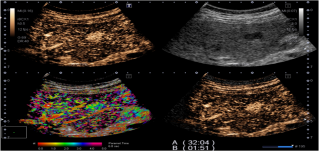

2. 全面的造影功能(Contrast Enhancement Ultrasound):系统可以四幅图(二维, 造影, 微血管累积模式MFI/到达时间参数成像P-MFI, 混合模式)同时显示,方便进行介入治疗方案的选择和即刻疗效的评估。

全面的造影模式包括以下几种模式:

血管识别成像(VRI)- 独有的技术

1. 方向性地观察肿瘤血管的走向,利于肿瘤新生血管的判断和分析及发现微小病灶。

2. 二维组织成像与造影剂灌注情况的同时显示。

3. 将造影剂的灌注状态以三种不同颜色同时显示,用红/蓝色方向性地显示较大血管的灌注,以绿色高分辨地显示微细血管的灌注,使得造影剂达到最佳的显示效果。

到达时间参数成像(P-MFI):

1. 对于具有不同血供特点的疾病方便的实施鉴别诊断。

2.对造影剂的灌注按时间顺序彩色编码,清晰显示微血管造影剂灌注。